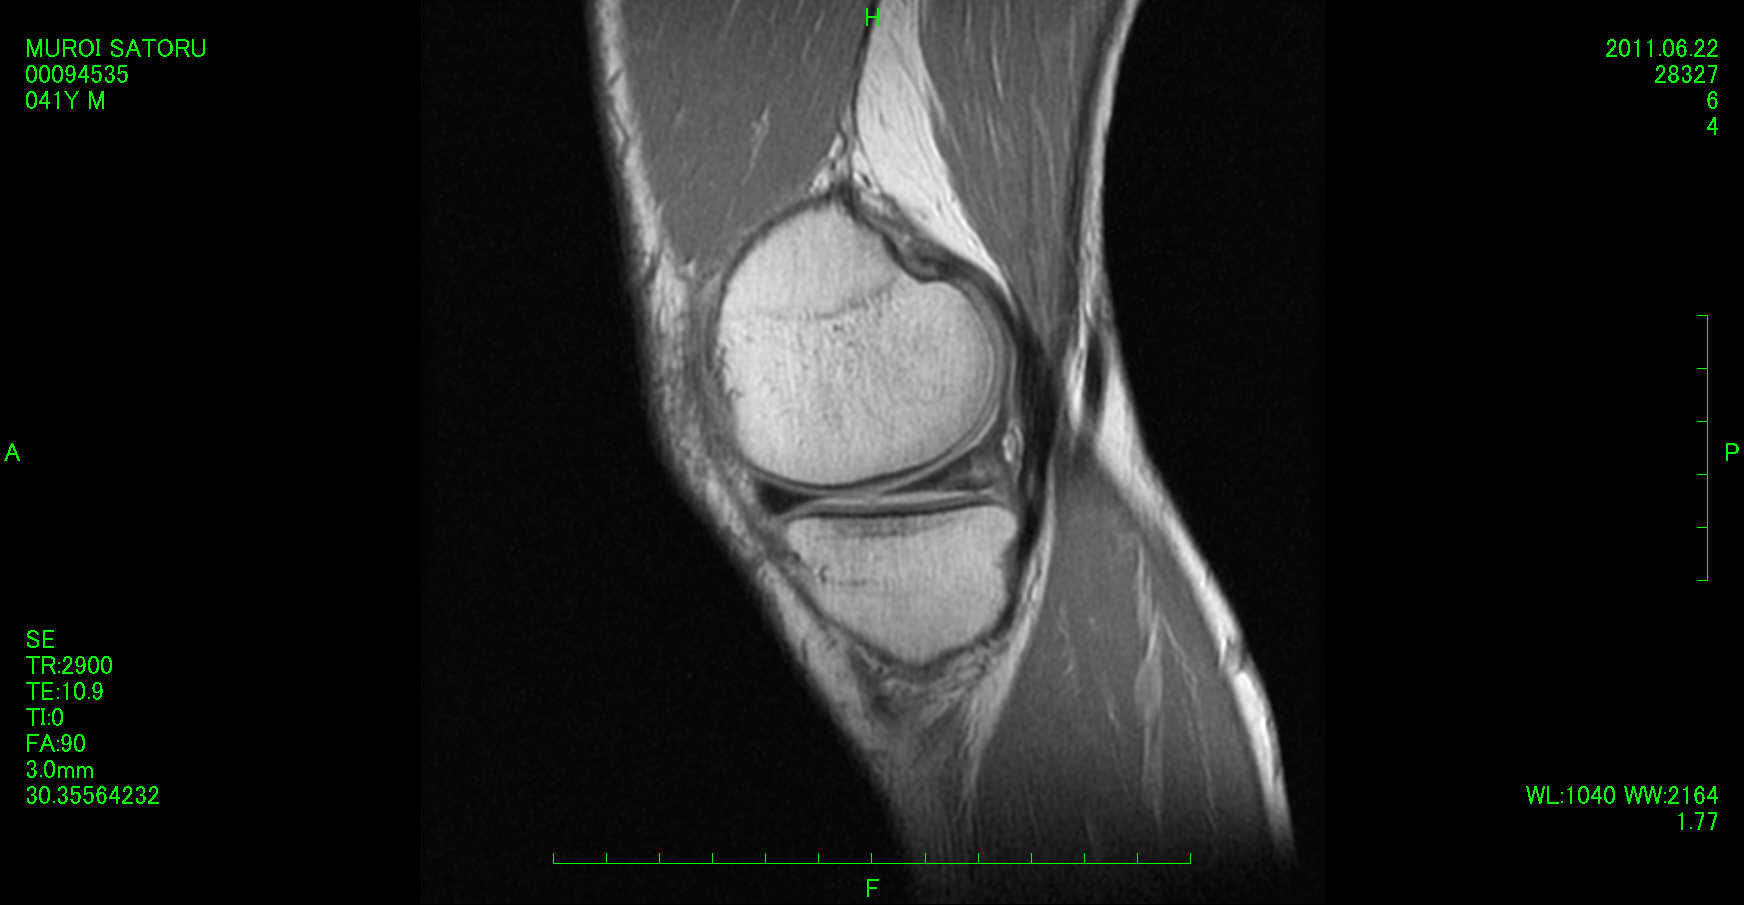

この部分をMRIで見てみましょう

まずT1矢状断(横から)で

内側半月板に白いもやもやが・・・

これは外傷による損傷でしょうか?

やはり損傷を思わせる輝度信号があるようですが

断裂のようなするどい線ではなくもやもやした感じ